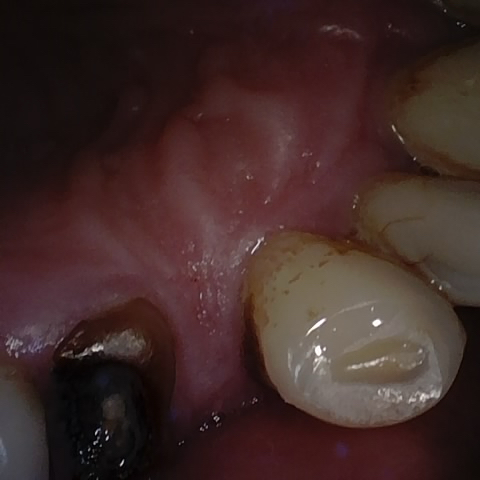

Annotated as "Good"